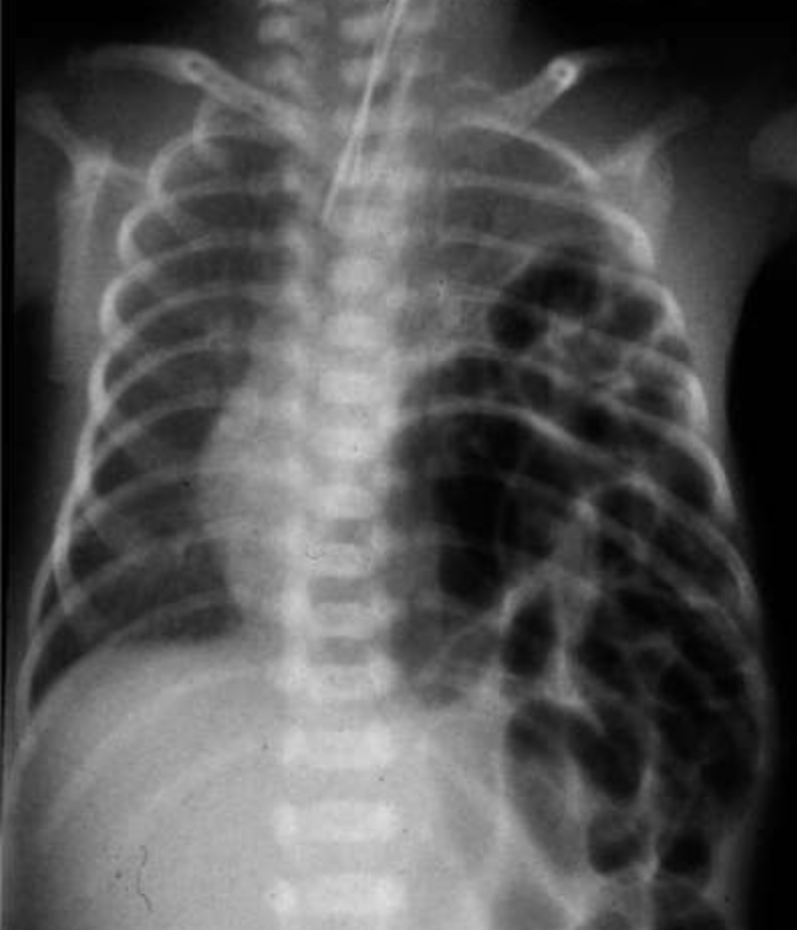

Case 25: Diaphragmatic Hernia

Case Study

Questions

- A- most important test

- ABG

- B- what is the diagnosis?

- Congenital diaphragmatic hernia

- C- what is the definitive treatment?

- Surgery

- D- give one association

- Lung hypoplasia

DIAPHRAGMATIC HERNIA:

- A newborn with left congenital diaphragmatic hernia. Note the scaphoid abdomen and the barrel-shaped chest.

Full-term baby normal vaginal delivery

- Shows severe respiratory distress. Air entry impaired in the left side, and heart apex heard in the right side.

- What is the cause of this respiratory distress? Left side massive diaphragmatic hernia.

- Treatment: Surgical repair